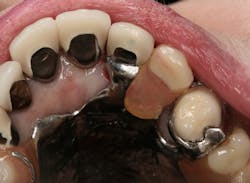

Figure 1: Occlusal image of finished root canal prep after gutta-percha removal

The root canal on No. 10 was completed using the WaveOne Gold system (Dentsply Sirona). Upon completed obturation, care was taken to remove only excess gutta percha from the canal using a warmed endodontic plugger. Removal extended approximately 4 mm to 5 mm into the canal space (figure 1).